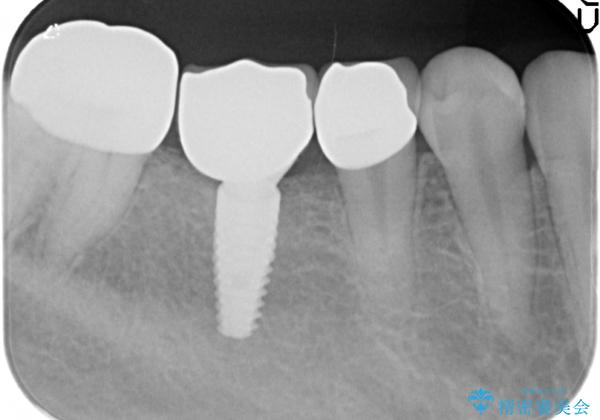

- 虫歯で歯を失い、インプラント治療を希望され来院されました。

吸収した骨を造骨にて補い、インプラントによる機能回復を計画します。

- 70万円(仮歯・ジルコニアクラウン×3 ストローマンインプラント・アバットメント)費用は治療当時の料金となります

歯を失ってからの時間が経過し骨が吸収してしまっていても、造骨を行うことで予知性の高いインプラント治療を行うことができます。